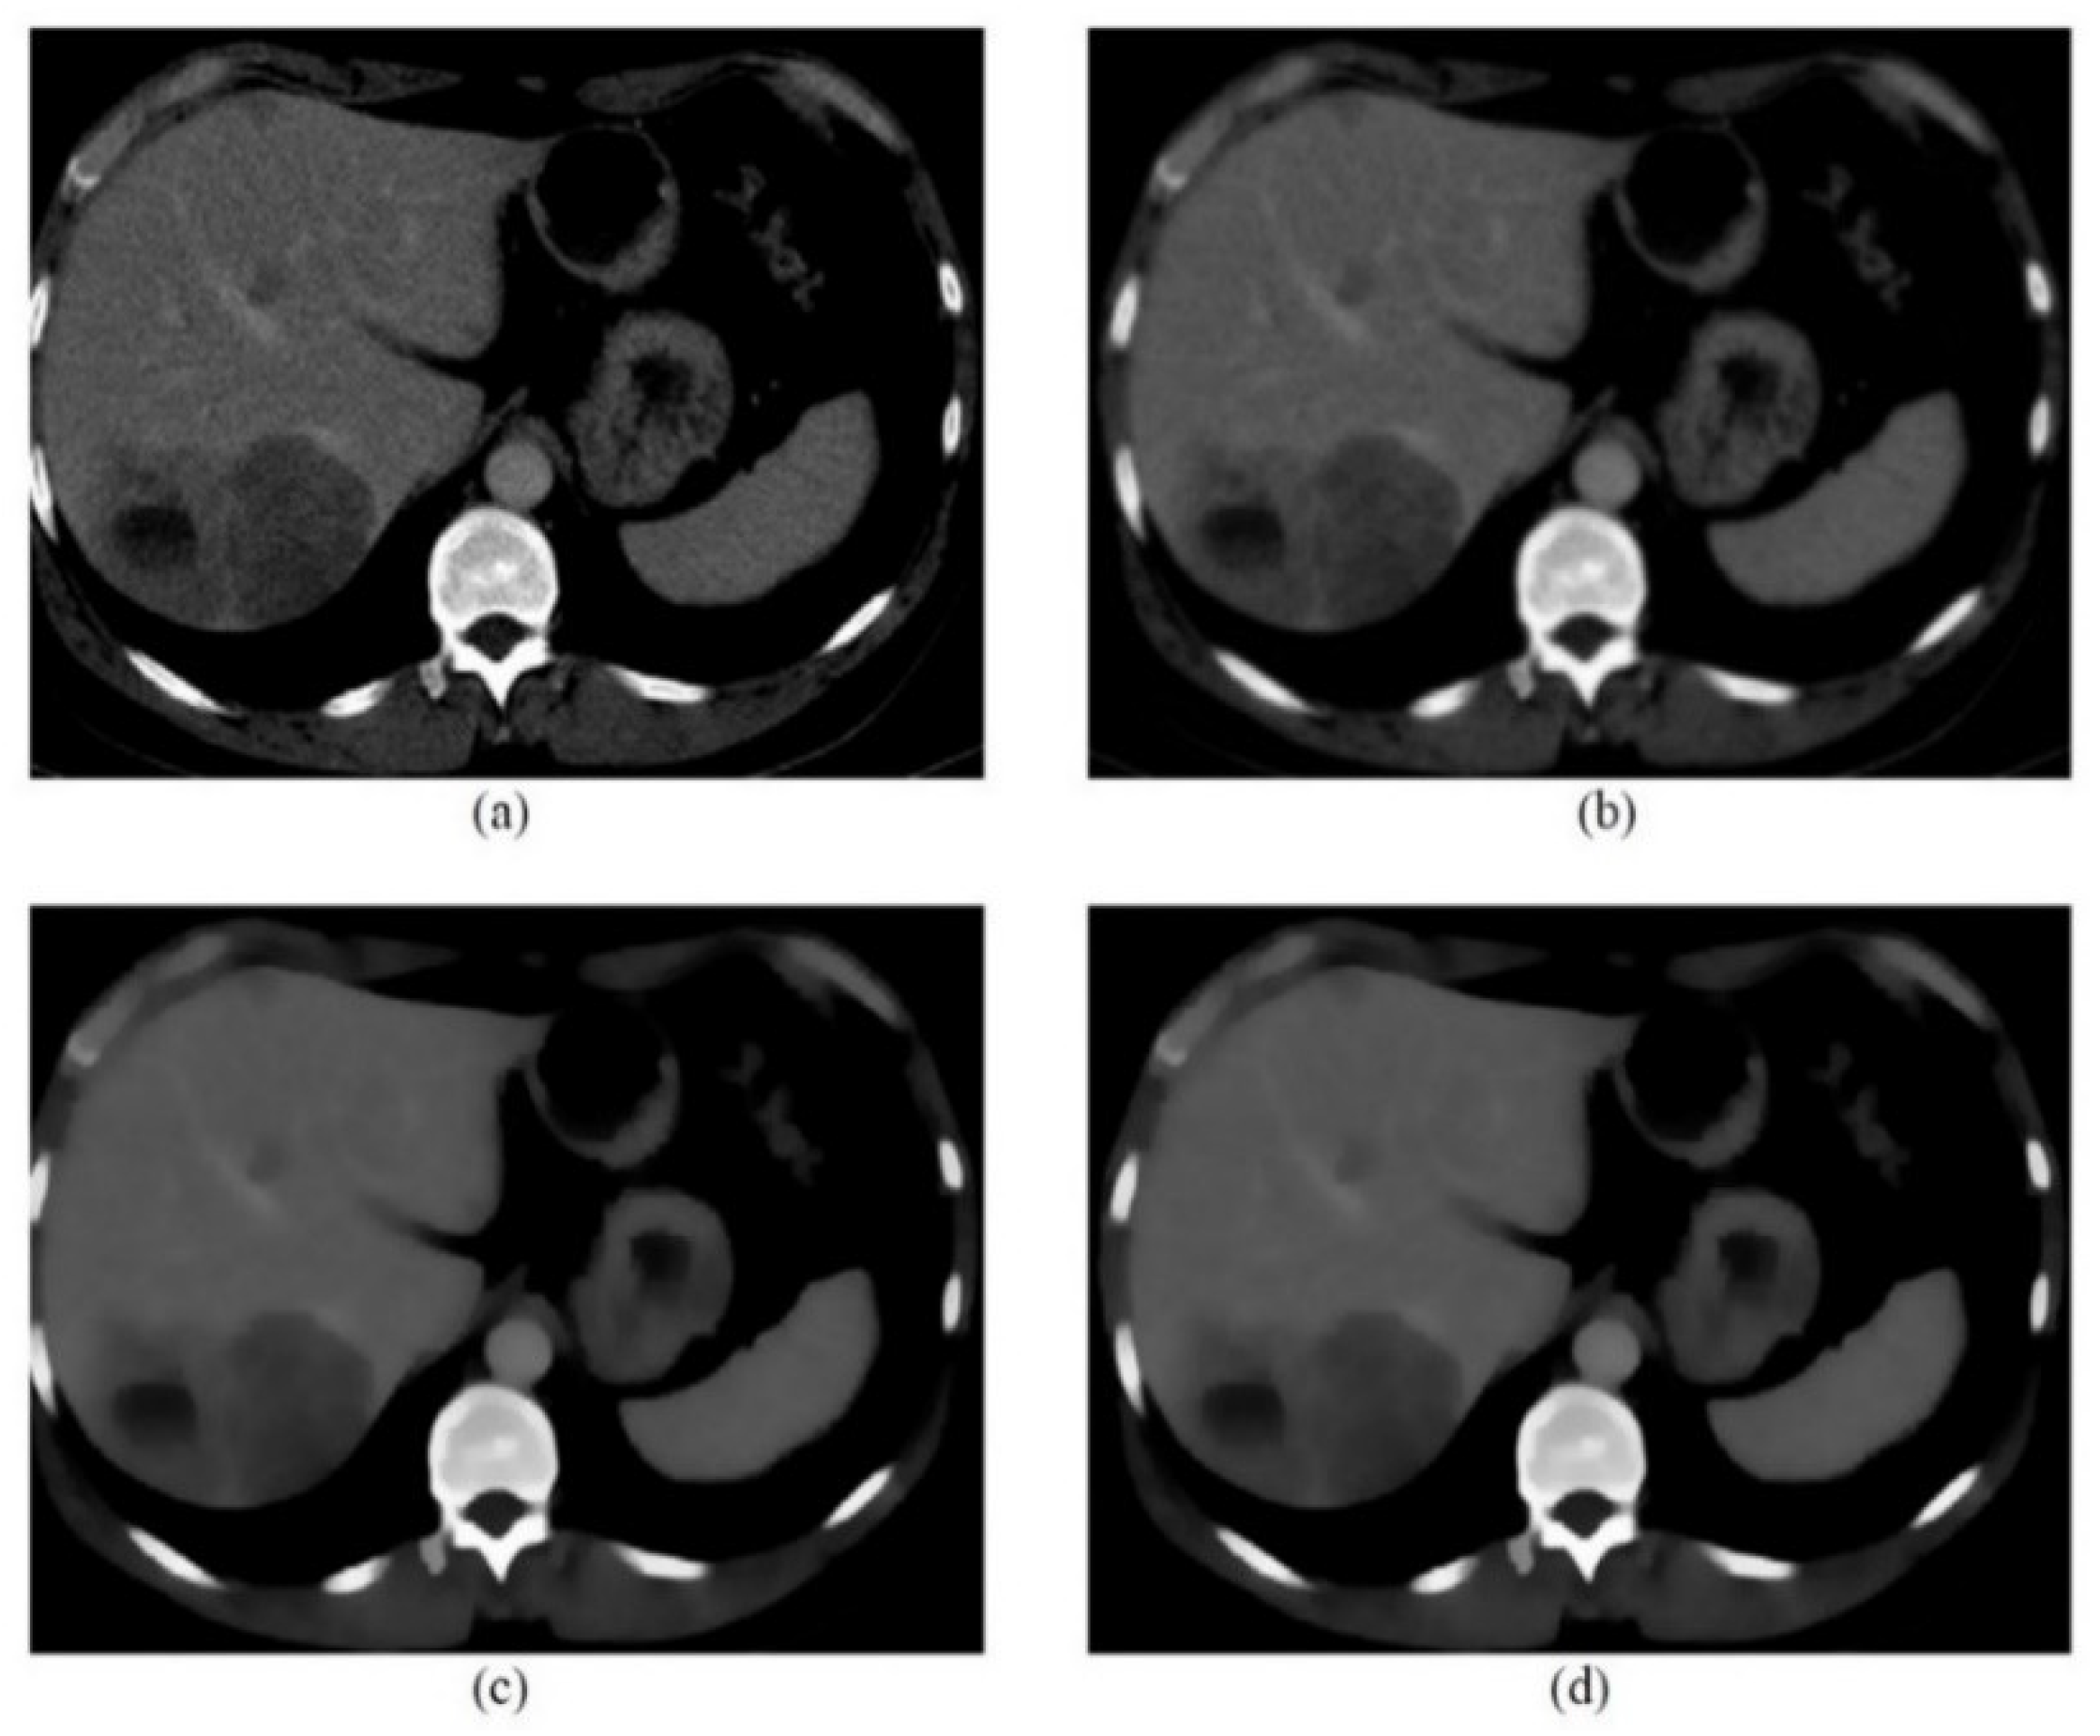

| CT image (Figure 6) 256 × 256 | 26.01 | 0.05 |

| CT image (Figure 7) 256 × 256 | 20.15 | 0.1 |

| CT image (Figure 8) 256 × 256 | 20.13 | 0.1 |

| CT image (Figure 9) 256 × 256 | 26.09 | 0.05 |

| CT image (Figure 10) 256 × 256 | 20.18 | 0.1 |

| CT image (Figure 11) 256 × 256 | 26.15 | 0.05 |